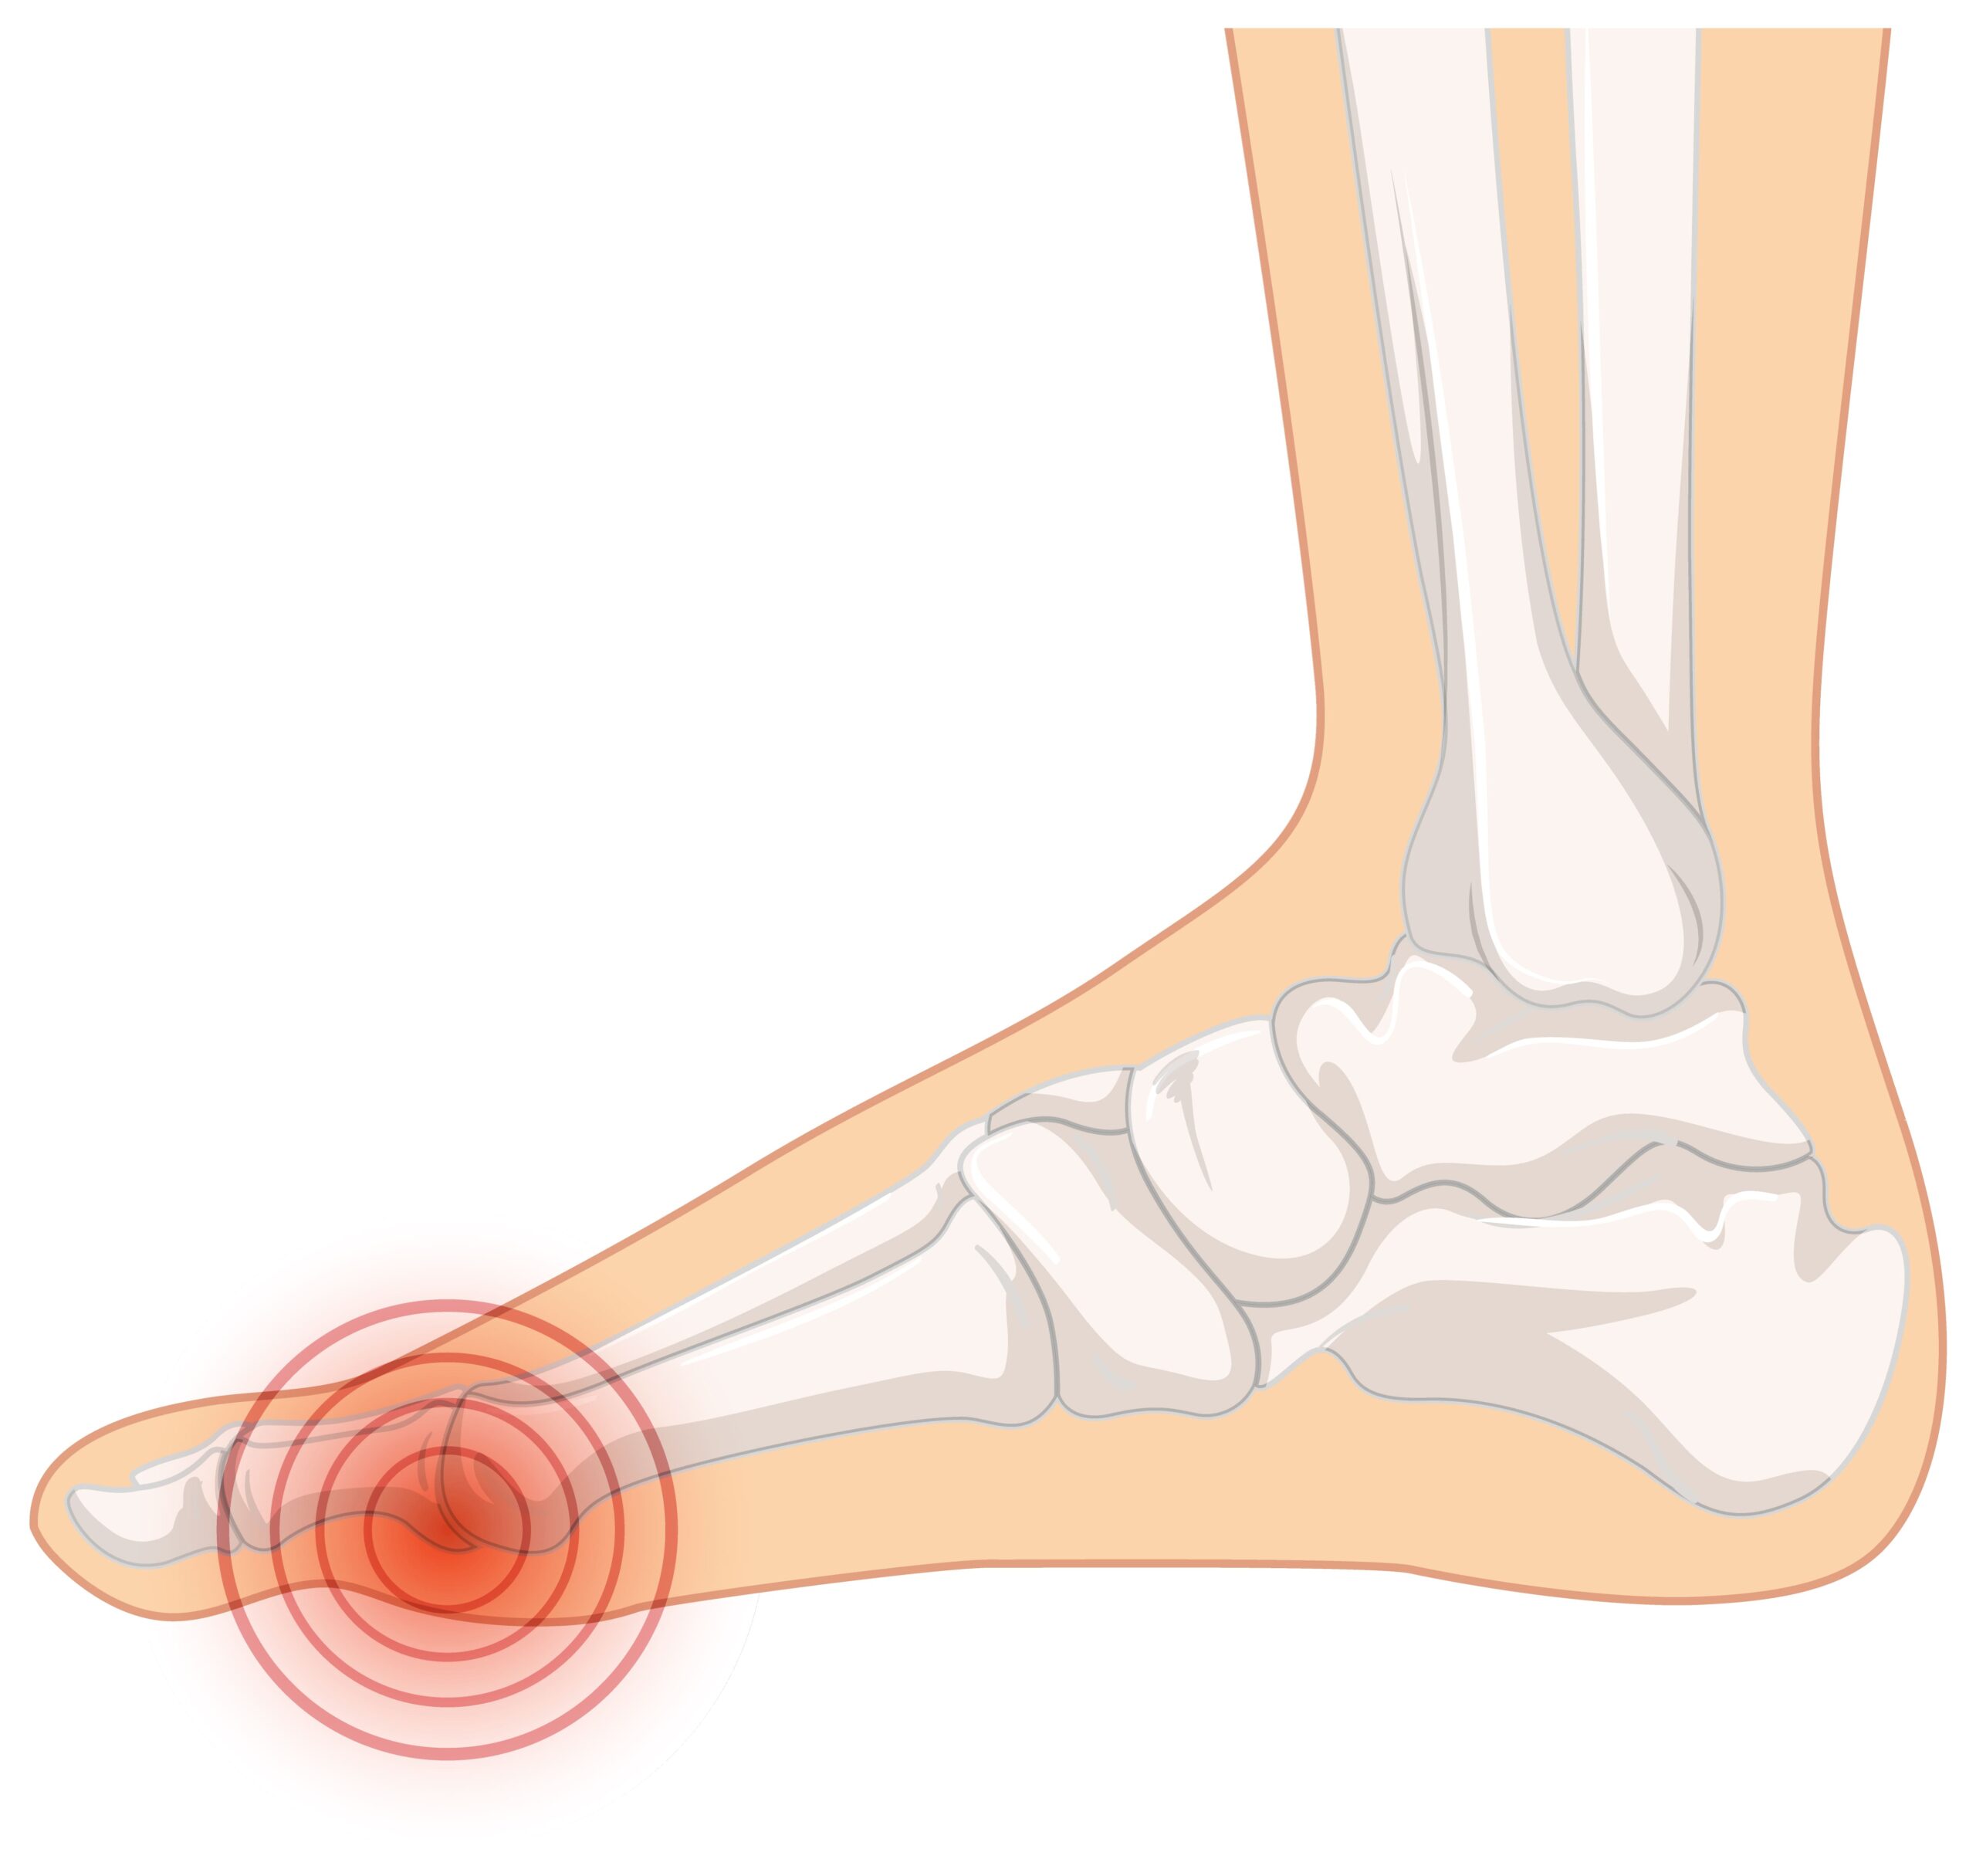

אם אתם חווים כאב חד, תחושת שריפה או הרגשה שאתם דורכים על "גולה" באזור הקדמי של כף הרגל (הכריות) – סביר להניח שאתם סובלים ממטטרסלגיה (Metatarsalgia). זהו מצב שבו מופעל לחץ עצום ובלתי פרופורציונלי על ראשי עצמות המסרק, מה שמוביל לדלקת, שחיקה וכאב יומיומי שמקשה מאוד על ההליכה והעמידה.

הטכנולוגיה – לראות את נקודת הלחץ המדויקת במטטרסלגיה, מילימטר אחד של חוסר דיוק במיקום הכרית המרופדת יעשה את ההבדל בין הקלה משמעותית לכאב מציק. לכן, אנו מבצעים בדיקת הליכה ממוחשבת (Gait Analysis) וסריקה תלת-ממדית (3D). הטכנולוגיה מציגה לנו "מפת לחצים" מדויקת בזמן תנועה (במיוחד בשלב הדחיפה של הרגל קדימה), ומאפשרת לנו למקם את התמיכה בנקודה המושלמת עבורכם.